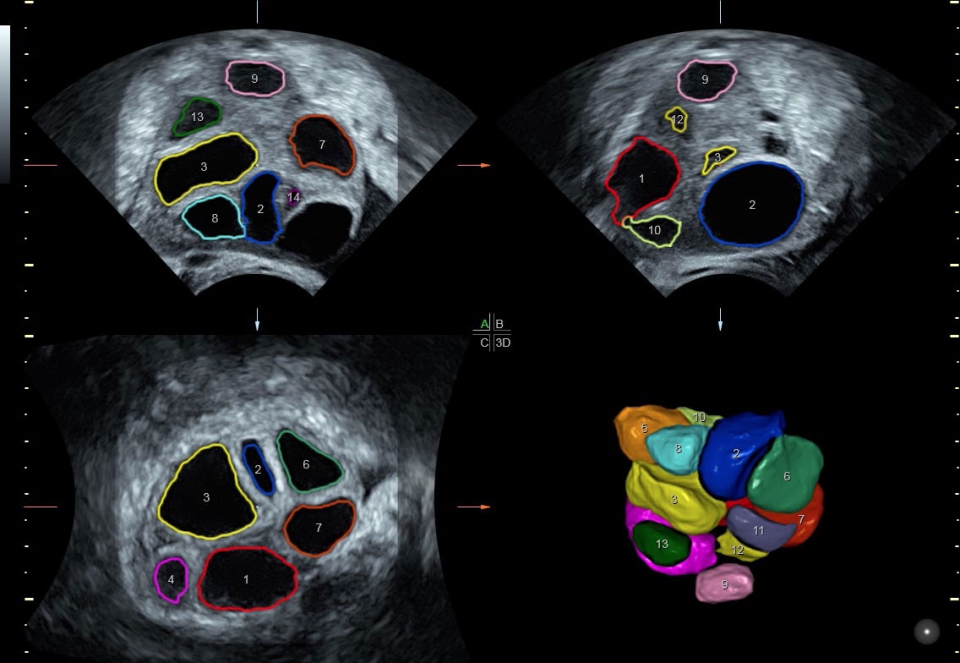

• SonoAVC (Автоматический расчет объема): Эта функция позволяет визуализировать и рассчитывать размеры и объем гипоэхогенных образований, таких как фолликулы яичника или структуры головного мозга плода. Она помогает в оценке этих образований и отслеживании их изменений в течение времени.

• SonoRenderlive (Автоматическое объемное изображение): Эта функция упрощает получение объемного изображения путем автоматического выбора положения плоскости визуализации для 3D- и 4D-режимов. Это сокращает необходимость вручную настраивать параметры и упрощает процесс получения объемных изображений.

• SonoVCADheart (Автоматическое получение серийных срезов сердца плода): При исследовании одного объема, эта функция позволяет получить 6 стандартизированных серийных срезов сердца плода одним нажатием. Это упрощает оценку структуры и функции сердца во время ультразвукового исследования.